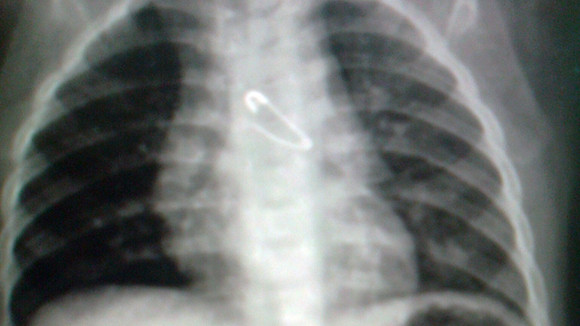

Hình ảnh X-quang ngực có kim băng

Tại BV Nhi Trung ương, kết quả chụp X-quang ngực thẳng và nghiêng cũng cho thấy có hình ảnh kim băng nằm trong đường thở, tận phế quản góc trái. Đặc biệt, kim băng ở trạng thái mở, đầu nhọn quay lên trên và ngập sâu vào niêm mạc phế quản. Sau khi hội chẩn, các bác sĩ đã quyết định mổ nội soi phế quản để lấy dị vật. Ca phẫu thuật diễn ra trong 2 giờ đồng hồ, hiện bệnh nhi đã bình phục, sức khỏe tốt và được xuất viện.